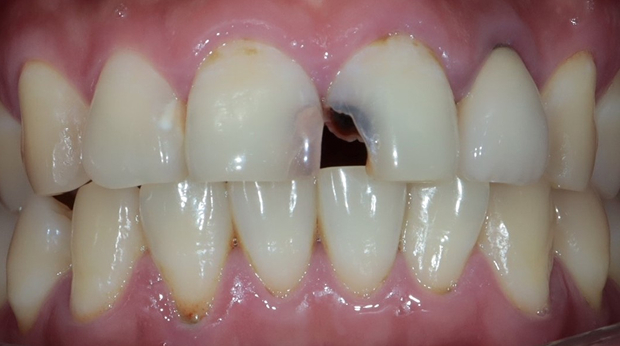

라미네이트